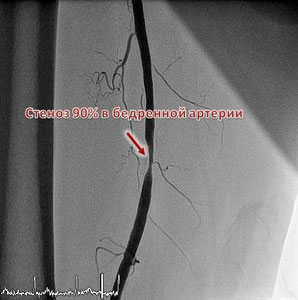

Стентирование артерий нижних конечностей

При сужении просвета сосудов нижних конечностей появляются трофические изменения, нарушения функции конечности (например, перемежающая хромота). Лечением этого заболевания является восстановление кровотока. Одной из операцией по восстановлению кровотока является стентирование артерий нижних конечностей. В нашем центра накоплен большой опыт выполнения стентирования артерий нижних конечностей. В своей работе мы используем инструменты и стенты последнего поколения и высочайшего качества. Это позволяет добиваться отличных результатов и быстрой реабилитации пациентов. Запись на консультацию - 8 (495) 201-68-33; 8 (499) 394-33-04.